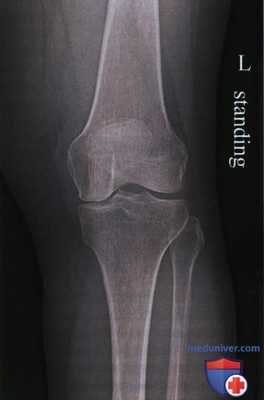

СНИМКИ КОЛЕННОГО СУСТАВА В ПРЯМОЙ ПРОЕКЦИИ

Назначение снимка. Рентгенографию коленного сустава производят во всех случаях заболеваний сустава и при травмах.

Укладки больного для выполнения снимков. Существует несколько вариантов укладки для выполнения этого снимка:

1. Чаще всего рентгенографию коленного сустава производят в прямой задней проекции. При этом больной лежит на спине, обе ноги вытянуты, сагиттальная плоскость стоп расположена перпендикулярно к плоскости стола. Кассету размером 18 х 24 см располагают в продольном положении. Проекция суставной щели, находящаяся при вытянутой ноге на 1,5—2 см ниже нижнего полюса надколенника, легко прощупываемого под кожей, соответствует средней линии кассеты. Пучок рентгеновского излучения направляют отвесно на центр кассеты (рис. 411).

Информативность снимка. На снимке коленного сустава в прямой задней проекции определяются дистальный метаэпифиз бедренной кости, медиальный и латеральный мыщелки бедра, между которыми располагается межмыщелковая ямка. Выше мыщелков определяются медиаль-ный и латеральный надмыщелки. На фоне дистального метаэпифиза бедренной кости виден надколенник. Проксимальный эпифиз большеберцовой кости представлен медиальным и латеральным мыщелками, между

которыми определяются медиальный и латеральный межмыщелковые бугорки. На латеральный отдел метаэпифиза большеберцовой кости частично накладывается головка малоберцовой кости. Между мыщелками бедренной и большеберцовой костей выявляется рентгеновская суставная щель коленного сустава в виде неравномерно изогнутой полосы просветления (рис. 415).

Информативность снимков коленного сустава как в задней прямой, так и в передней прямой проекциях одинаковая. В передней прямой проекции несколько лучше видна структура надколенника. Информативность одномоментных снимков коленных суставов в прямой задней проекции ниже, так как каждый из суставов при этом подвергается проекционным искажениям.